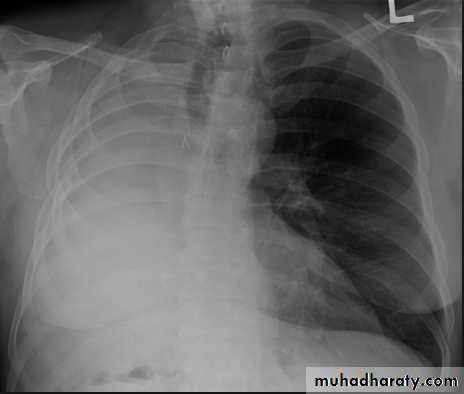

Tension pneumothorax.

On a posteroanterior chest x-ray (A), the left hemithorax is very dark or lucent because the left lung has collapsed completely (white arrows).

The tension pneumothorax can be identified because the mediastinal contents, including the heart, are shifted toward the right, and the left hemidiaphragm is flattened and depressed. A computed tomography scan done on a different patient with a tension pneumothorax (B) shows a completely collapsed right lung (arrows) and shift of the mediastinal contents to the left.